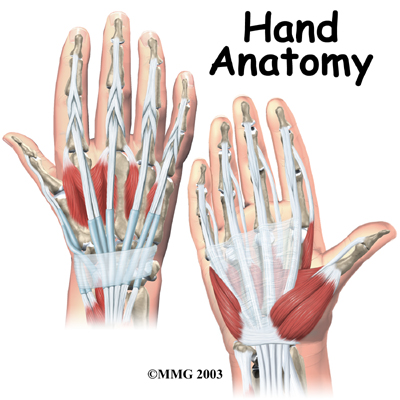

Muscles

Many of the muscles that control the hand start at the elbow or forearm. They run down the forearm and cross the wrist and hand. Some control only the bending or straightening of the wrist. Others influence motion of the fingers or thumb. Many of these muscles help position and hold the wrist and hand while the thumb and fingers grip or perform fine motor actions.

Most of the small muscles that work the thumb and pinky finger start on the carpal bones. connect in ways that allow the hand to grip and hold. Two muscles allow the thumb to move across the palm of the hand, an important function called .

The smallest muscles that originate in the wrist and hand are called the intrinsic muscles. The intrinsic muscles guide the fine motions of the fingers by getting the fingers positioned and holding them steady during hand activities.